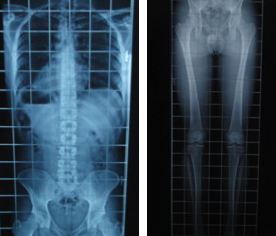

Dismetría. Qué son las dismetrías de miembros inferiores

La diferencia de longitud entre una pierna y otra puede generar problemas biomecánicos . ¿Qué son las Disimetrías? En este breve artículo queremos…